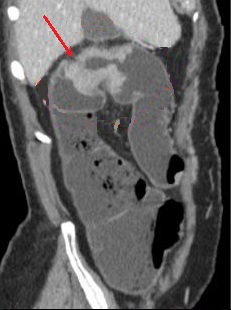

Meme cas

en coupe sagitale . Image radiologioque de coloCT a

l'eau en coupe sagitale . |